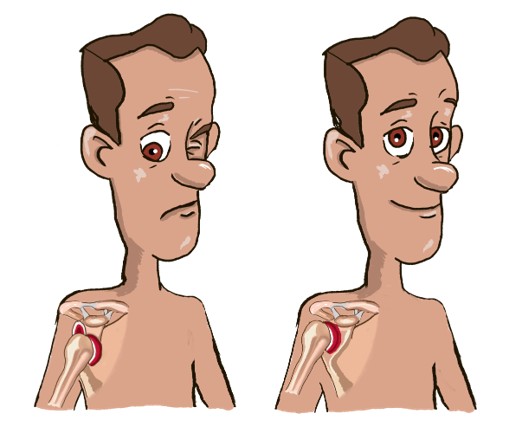

Κάταγμα

Συμπτώματα:

- Παραμόρφωση

- Οίδημα

- Έντονος πόνος με ή χωρίς κίνηση

- Εκχύμωση

- Προεξέχον οστό

Πρώτες Βοήθειες:

- Συνοδεία ανοιχτού τραύματος & σοβαρής αιμορραγίας, εφαρμογή Ά Βοηθειών για Απειλητική για τη Ζωή Αιμορραγία

- Κλήση112/166 άμεσα αν το άκρο είναι μπλε, μωβ ή ωχρό

- Κάλυψη με καθαρό επίθεμα

- Ακινητοποίηση του άκρου μόνο από εξειδικευμένο προσωπικό